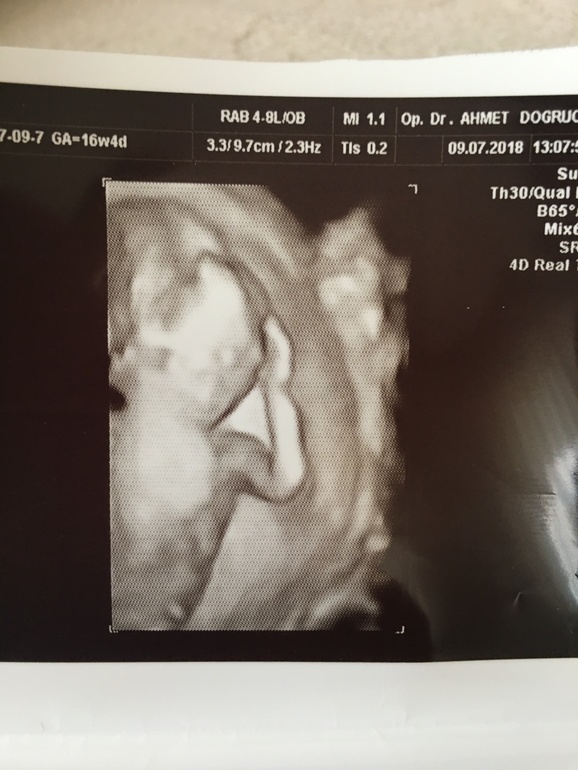

Мария 7 лет Наши первые фото сыночка Для себя на память) 17 неделя ) 17 неделя Посмотрите еще 20 записей на эту тему Отменить Ответить Светочка поздравляю!!! 08.08.2018 Ответить Мария Света, спасибо огромное!! 08.08.2018 Ответить 21 неделя) сынок мы ждём тебя очень!!! 20 неделя! Фото: привет Мама и Папа!) Чаты Беременных Выберите чат: Январята-2026 Февралята-2026 Мартята-2026 Апрелята-2026 Майчата-2026 Июнята-2026 Июлята-2026 Августята-2026